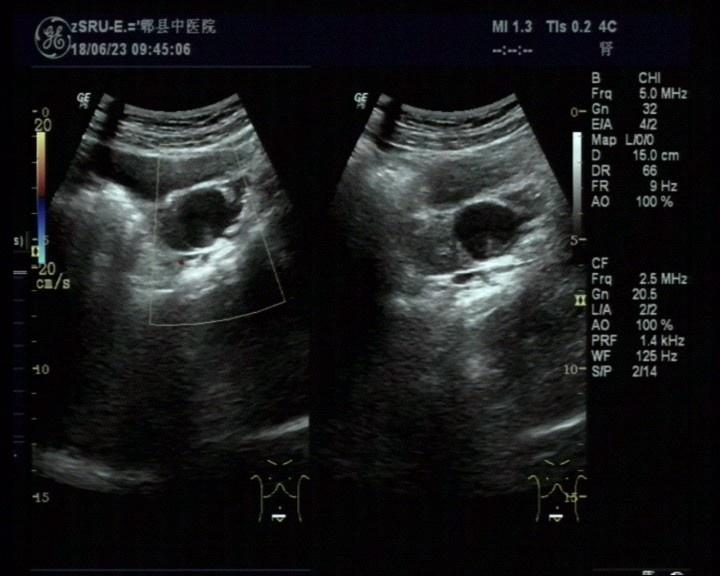

右侧附件区畸胎瘤可能

女,30岁,既往体检无异常,此次超声检查如图所示:右侧附件区探及一杂乱不均回声团,边界清楚,形态规则,CDFI:周边可见少许血流信号。